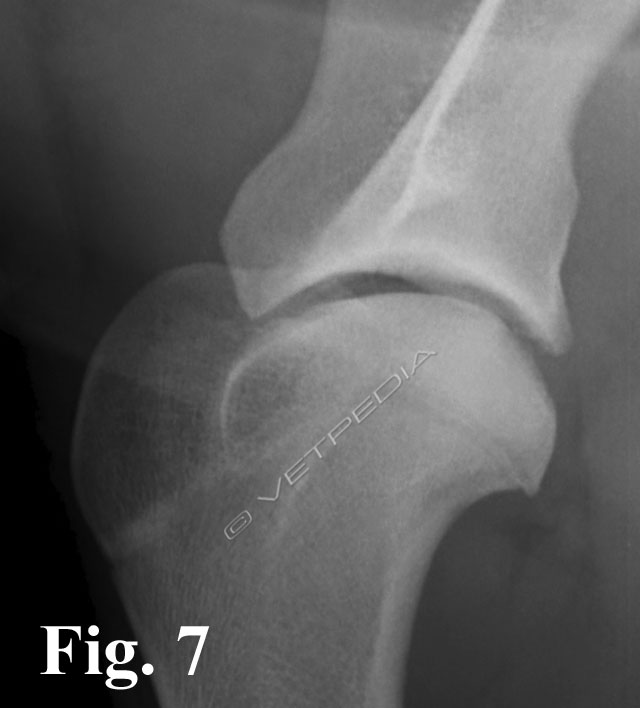

In caso di osteocondrite dissecante (OCD) si verifica una fissurazione nella parte ispessita della cartilagine ed il sollevamento di un lembo osteocondrale, seguito dall’esposizione di osso subcondrale (Fig. 1). Il movimento eccessivo o i microtraumi derivanti dalla normale attività fisica possono determinare il distacco completo del lembo osteocondrale, che diviene corpo libero articolare. Quest’ultimo può andare incontro a destini differenti: molto raramente può riassorbirsi, può dislocarsi nel fondo cieco caudale (cul di sac) o prossimalmente nella doccia bicipitale. Il lembo può accrescersi e calcificare traendo nutrimento dalla vascolarizzazione sinoviale e divenire visibile radiograficamente (Fig. 2). Il contatto del liquido sinoviale con l’osso subcondrale scatena un insieme di reazione biochimiche e biologiche che porta alla formazione di sinovite, momento in cui generalmente si osservano i primi sintomi clinici. Anche il lembo osteocondrale quando diviene corpo libero può svolgere un’azione continua d’irritazione e divenire concausa dello sviluppo di sinovite. Il difetto cartilagineo viene riparato dalla formazione di fibrocartilagine.

Alla visita ortopedica apprezziamo algia all’esecuzione dei movimenti passivi dell’articolazione. Con il cronicizzarsi della lesione osserviamo un diverso grado di ipomiotrofia dei muscoli della spalla. Il sospetto diagnostico emesso dalla visita clinica viene confermato mediante l’esecuzione di uno studio radiografico dell’articolazione della spalla. Per emettere una diagnosi è generalmente sufficiente eseguire una proiezione medio-laterale della spalla, avendo l’accortezza di esercitare una trazione sulla zampa in modo da scostare l’articolazione dalla sovrapposizione radiografica dello sterno. Considerando la frequente bilateralità della lesione, è doveroso eseguire un controllo dell’arto contro laterale, in modo da non trascurare quelle lesioni ancora clinicamente asintomatiche o paucisintomatiche. L’esame radiografico evidenzia un difetto del profilo del terzo caudale della testa omerale (Fig. 3). In alcuni casi è possibile visualizzare il lembo osteocondrale sollevato ma ancora in sede (vedi Fig. 1), in altri casi si può osservare solo un aumento della radiotrasparenza dell’osso subcondrale, più o meno esteso. Alcune forme iniziali di osteocondrosi (OC), non ancora evolute in osteocondrite dissecante (OCD), si manifestano radiograficamente come dei piccoli appiattimenti del profilo tondo della testa omerale, senza modificazioni della densità omogenea sub condrale (Fig. 4).